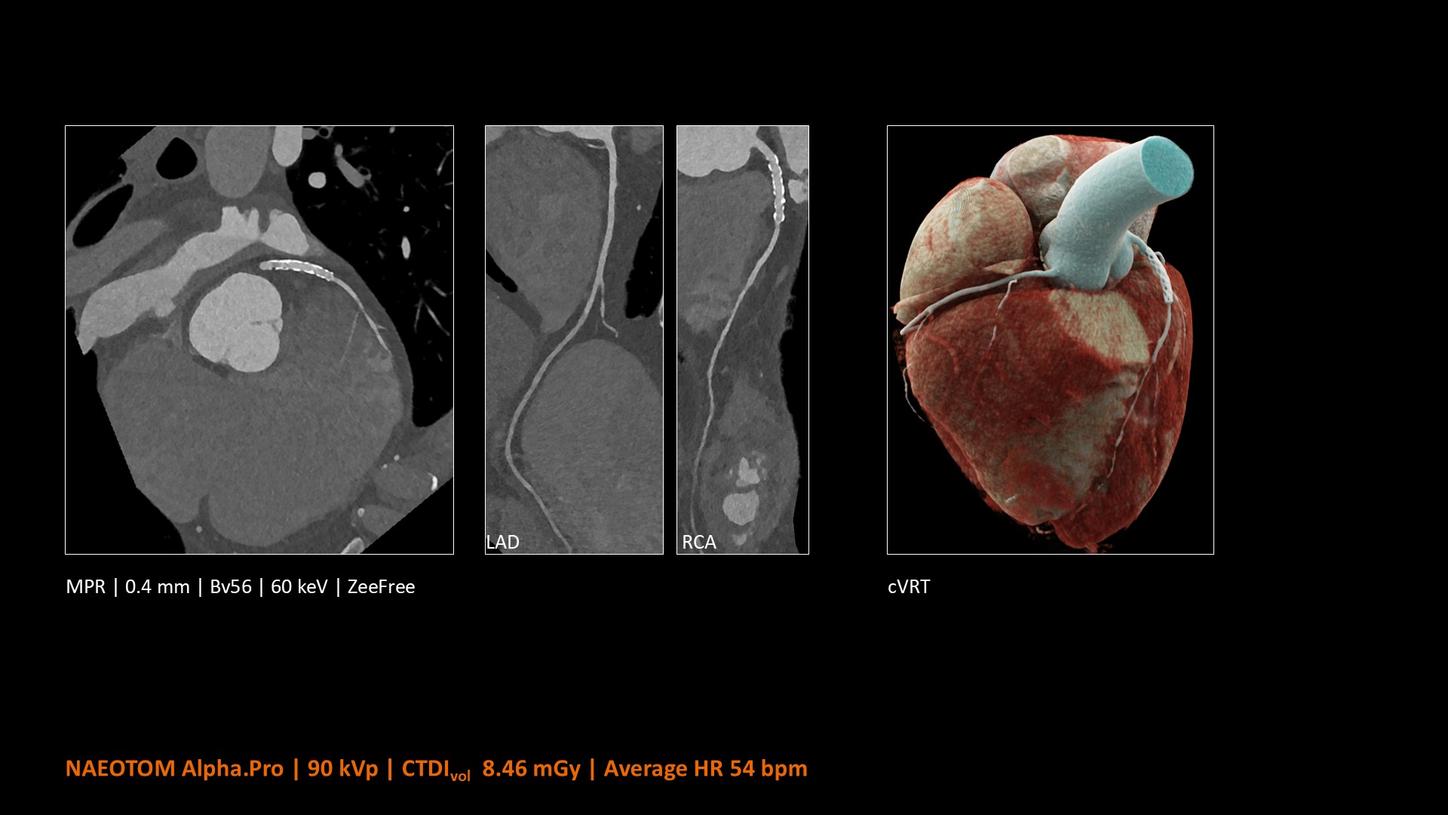

NAEOTOM Alpha® con Quantum Technology®, la nostra nuovissima Dual Source photon-counting CT, offre immagini Quantum HD Cardiac con uno spessore di slice di 0,2 mm. In questo modo è possibile visualizzare dettagli del cuore precedentemente non rilevabili senza incrementi di dose. Inoltre, le informazioni spettrali sono automaticamente disponibili in ogni scansione grazie a un processo di conversione diretta che trasforma i singoli fotoni dei raggi X in un segnale elettrico per creare l'immagine.

Quantum Technology consente una migliore valutazione diagnostica dei vasi coronarici nella TC. Secondo un recente studio, NAEOTOM Alpha e Quantum HD Cardiac potrebbero aver contribuito a ridurre la necessità di un'angiografia coronarica invasiva per il 54% dei pazienti nel rilevamento della malattia coronarica in una popolazione ad alto rischio.¹

Il Dott. Bálint Szilveszter, MD, PhD, presso la Semmelweis University a Budapest, in Ungheria, condivide I benefici dell’elevata risoluzione spaziale e della valutazione della placca con la TC photon counting e come questi permettano una maggior confidenza diagnostica nella valutazione dei disturbi alle coronarie (CAD)